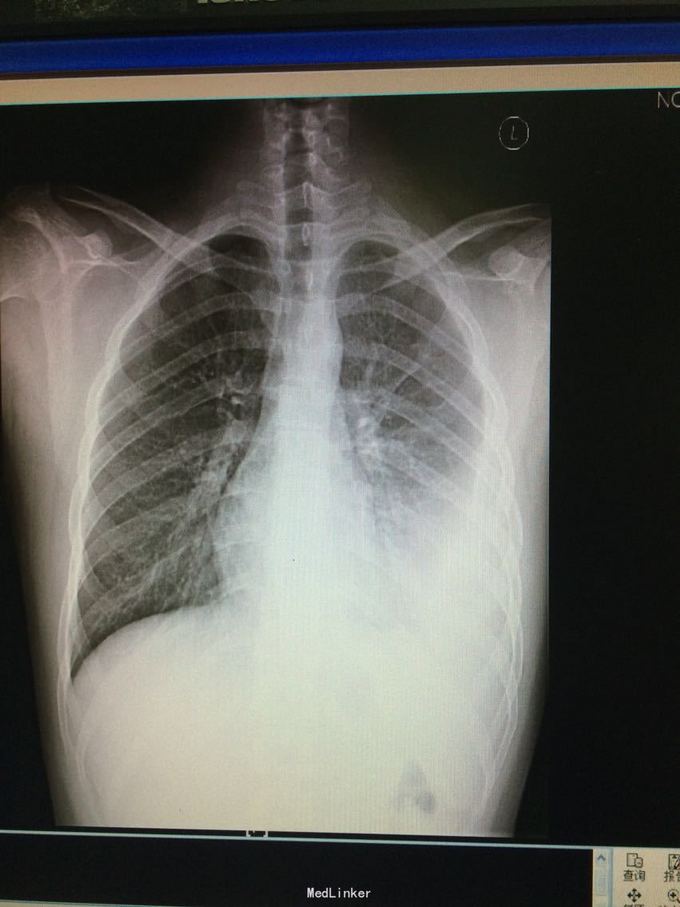

16岁男性,既往体健。 主诉:发热5天。 现病史:5天前无明显诱因出现反复发热,T波动在38-39度,伴畏寒、寒战,无咳嗽、咳痰。我院急诊胸片示:左肺炎症,左侧少量胸腔积液。遂入院。

查体:左下肺呼吸音减弱,双肺未及明显干湿啰音。 辅查:床边B超示左侧胸腔积液,最大前后径40mm。血常规、PPD、结核抗体正常,CRP 145mg/l,ESR 61mm/h,T-spot阳性。予胸腔穿刺术,引流出黄色液体,实验室检查示炎性渗出液。

诊断:结核性胸膜炎。 入院后先予头孢唑肟、阿奇霉素抗感染治疗,体温无明显下降。3天后结合患者胸水性质,改予异烟肼、利福平、吡嗪酰胺、乙胺丁醇抗结核治疗,体温可降至正常。

随访:未能引流胸水后,查胸部CT未见明显肺部病灶。继续予抗结核治疗并予出院。 讨论:目前治疗效果支持结核性胸膜炎诊断。患者症状不支持结核,但就年龄、胸水性质而言,高度支持结核感染。临床中很多疾病都不像教科书那般典型,需注意。